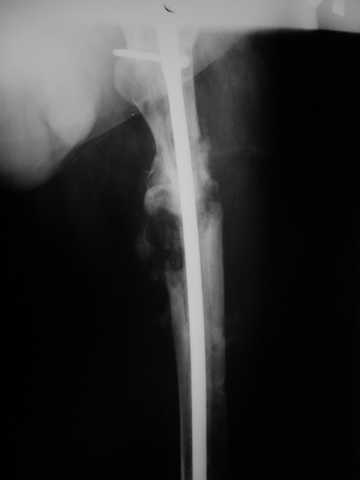

Мы демонтировали спице-стержневой аппарат, рассверлили костно-мозговой канал (до 14 мм), установили в канал спейсер с антибиотиком и произвели его блокирование четырьмя винтами ( рис. 1, 2, 3, 4).

В качестве армирующего элемента для спейсера мы использовали титановый неканюлированный штифт типа UFN (диаметр 9 мм, длина 400 мм). Проксимальную широкую часть штифта костным цементом не покрывали (рис. 5).

Дистальные блокирующие отверстия в цементе рассверлили после его застывания под ЭОП'ом. В проксимальном отломке использовали винт-полер (так как штифт проходил очень близко к переднему кортикальному слою).